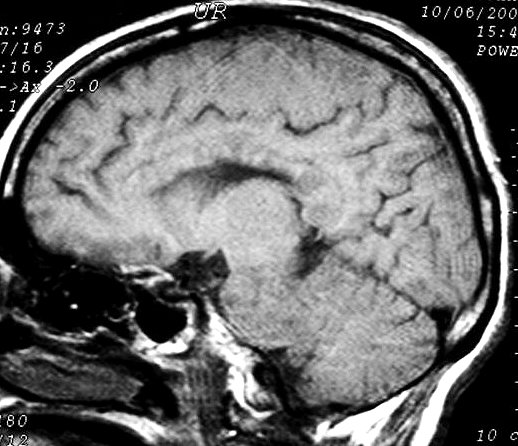

ГМ. Рассеянный склероз 2. +

Рассеянный склероз